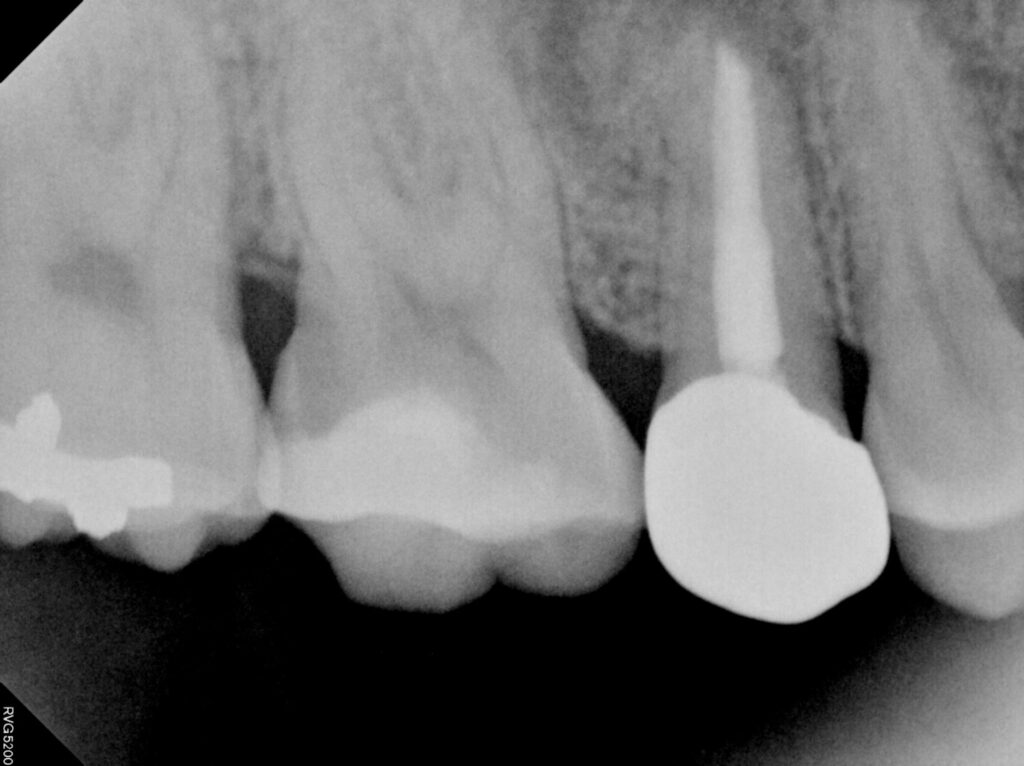

환자분께서는 신경치료 후 크라운을

진행하지 않았던 오른쪽 위 작은 어금니

뿌리의 큰 낭종이 생겨 있는 상태였는데요.

위턱뼈의 3개 치아가 넘는 크기의

낭종으로 제거가 필요한 상황임을

설명드리고 치료 계획을 수립하였습니다.